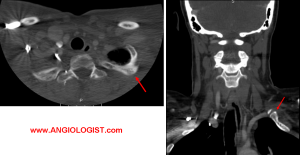

- Arterial TOS manifests as emboli that are showered distally from the area of compression. A common mechanism is repeated injury. In sports this is typical of overhead pitchers. Most often a digit or the whole hand are affected, with more proximal symptoms possible, but less common. Thus, arterial thoracic outlet syndrome is different than the other types in that symptoms are more distal, while neck pain and scalene muscle tenderness are absent. Imaging such as duplex ultrasound or CT angiography can often demonstrate the focal arterial flaws that are the source of the emboli (such as aneurysm formation).